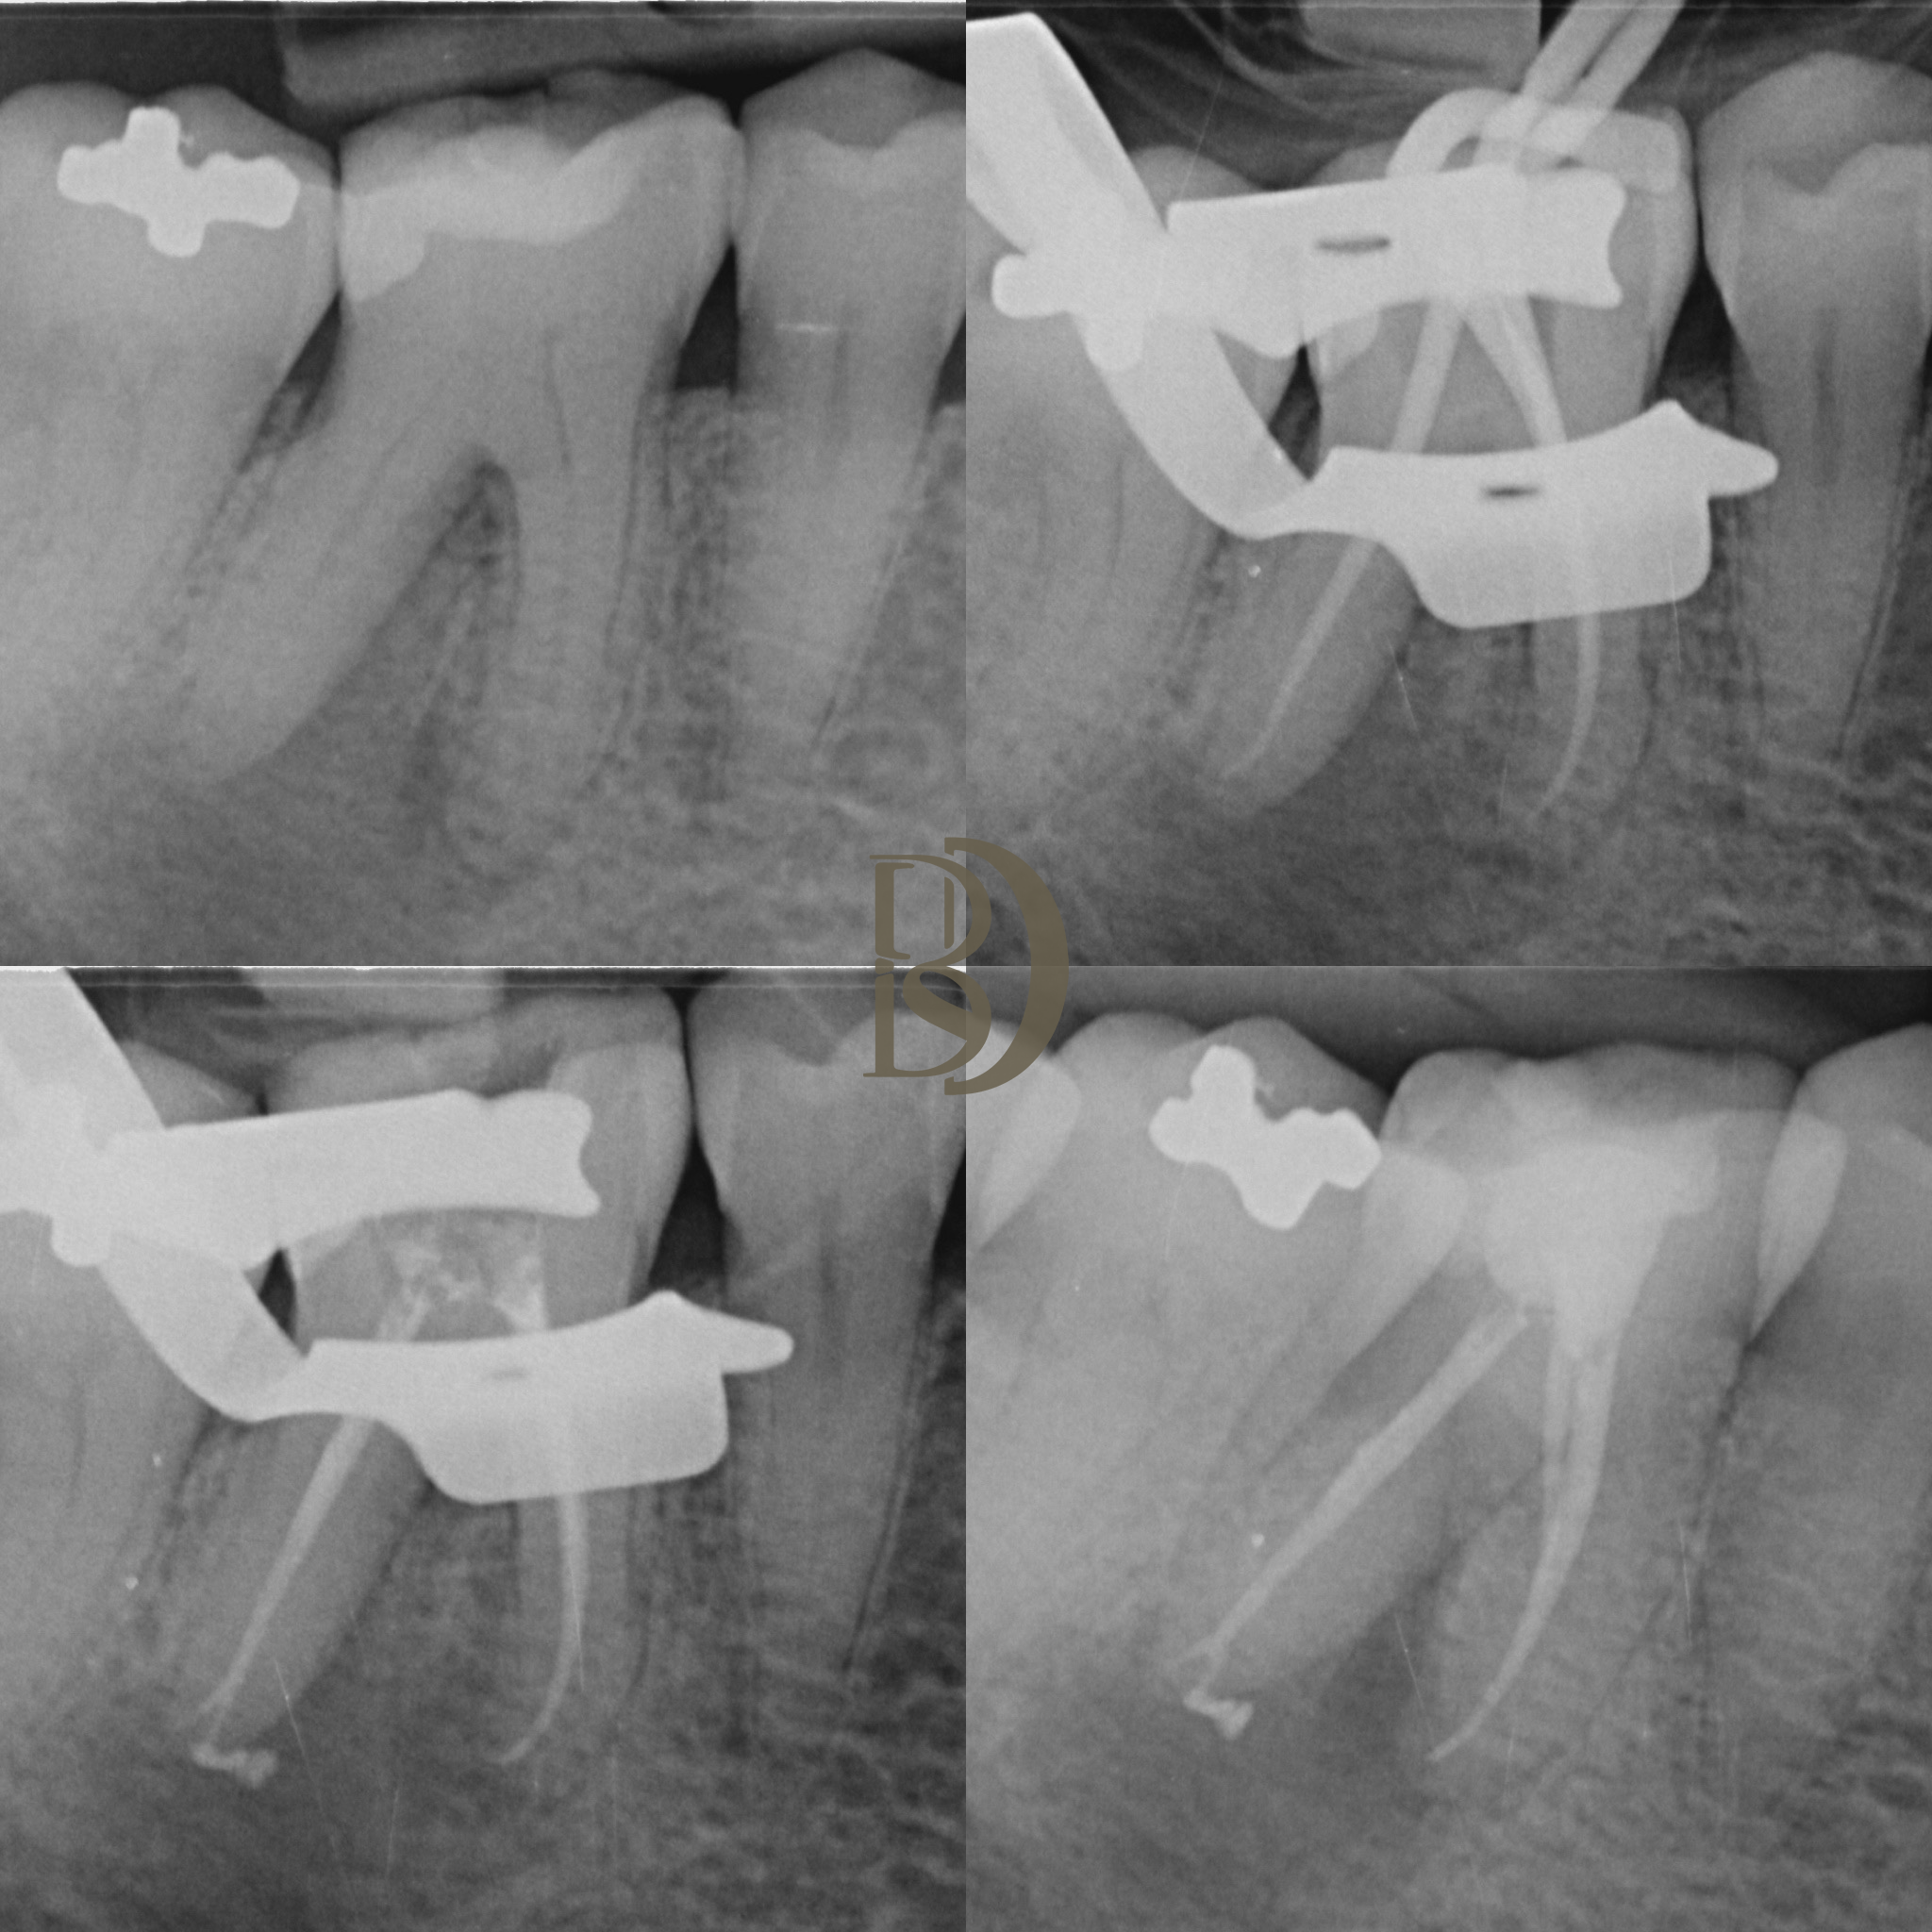

Some examples of Dr Fred’s Endodontic cases:

X-ray images showing dental and endodontic procedures on molar teeth.